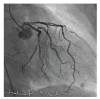

Takotsubo cardiomyopathy (TCM) is usually characterized by transient left ventricular apical ballooning. Due to the clinical symptoms which include chest pain, electrocardiographic changes, and elevated myocardial markers, Takotsubo cardiomyopathy is frequently mimicking ST-elevation myocardial infarction in the absence of a significant coronary artery disease. Otherwise an acute occlusion of the left anterior descending coronary artery can produce a typical Takotsubo contraction pattern. ST-elevation myocardial infarction (STEMI) is frequently associated with emotional stress, but to date no cases of STEMI triggering TCM have been reported. We describe a case of a female patient with inferior ST-elevation myocardial infarction complicated by TCM.